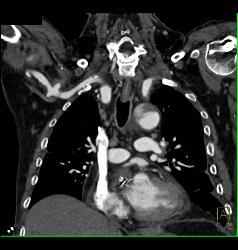

Pulmonary Embolism (PE) in Left Lobe Lung